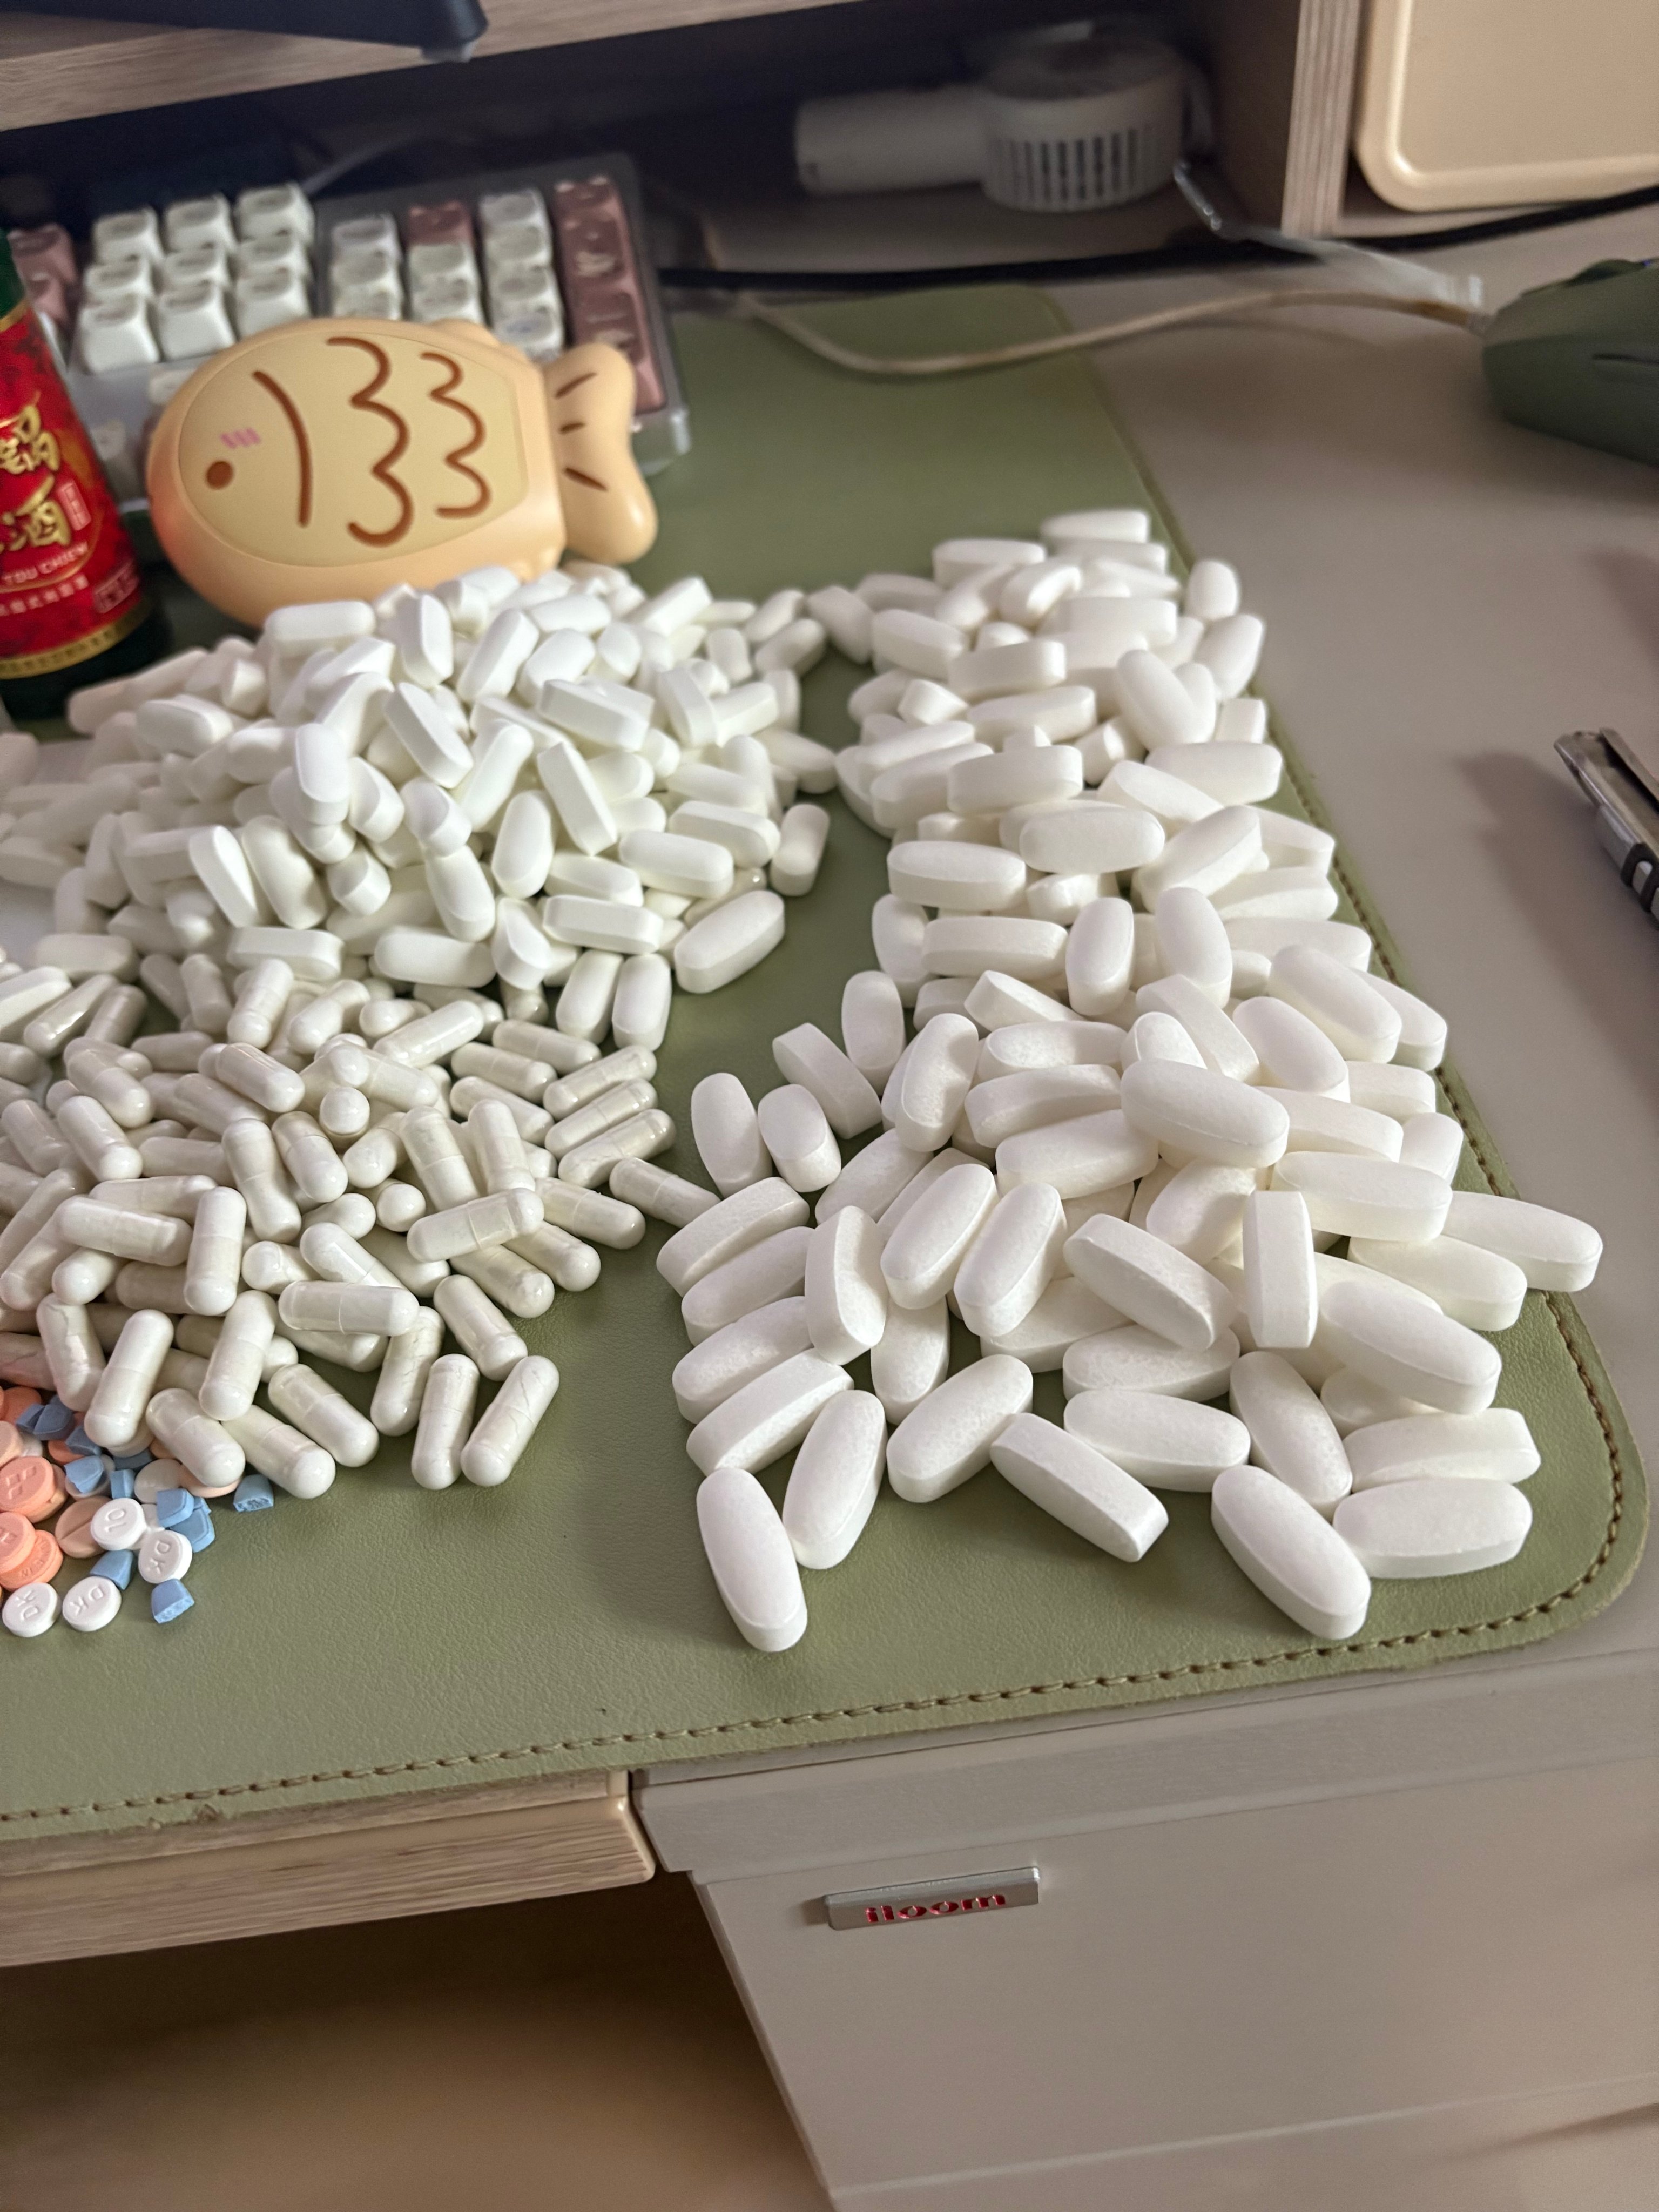

对于药物过量引起的中枢神经系统副作用,有一些不常见或常见的药物来控制症状。

喹硫平:不清楚是什么引起的症状就干脆谁都别玩了吧()似乎很万能的急救